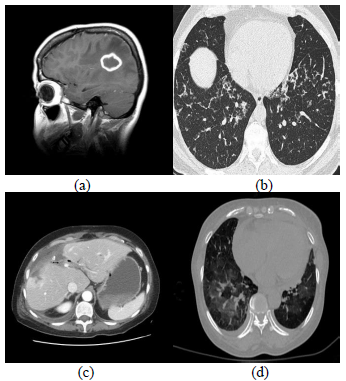

The proposed technique has been tested on different low contrast medical images. The simulations have been performed with MATLAB R2018a. We used sample of dataset of medical images shown in Figure 1. The goal is to efficiently segment an image in three different levels. Note that “for n-levels segmentation problem the dimensionality of the search space is D=2*(n-1) as number of unknown fuzzy parameters are 2”. To verify the efficiency of the proposed segmentation approach, we compare our method with Tao et al. [21] and Tang [22]. Experiments have been carried using low contrast medical images. In this section various types of dataset, including images of human brain, Lung and Liver have been employed. In our experimental, “we first present the comparison results of the proposed approach using different three level of threshold”. Subsequently, the results for Tao et al. [21] and Tang [22] have been provided. Finally, Table 1 has been given to show the “details of parameters obtained in the experiments of the proposed approach”.

Figure 1. Sample of medical images